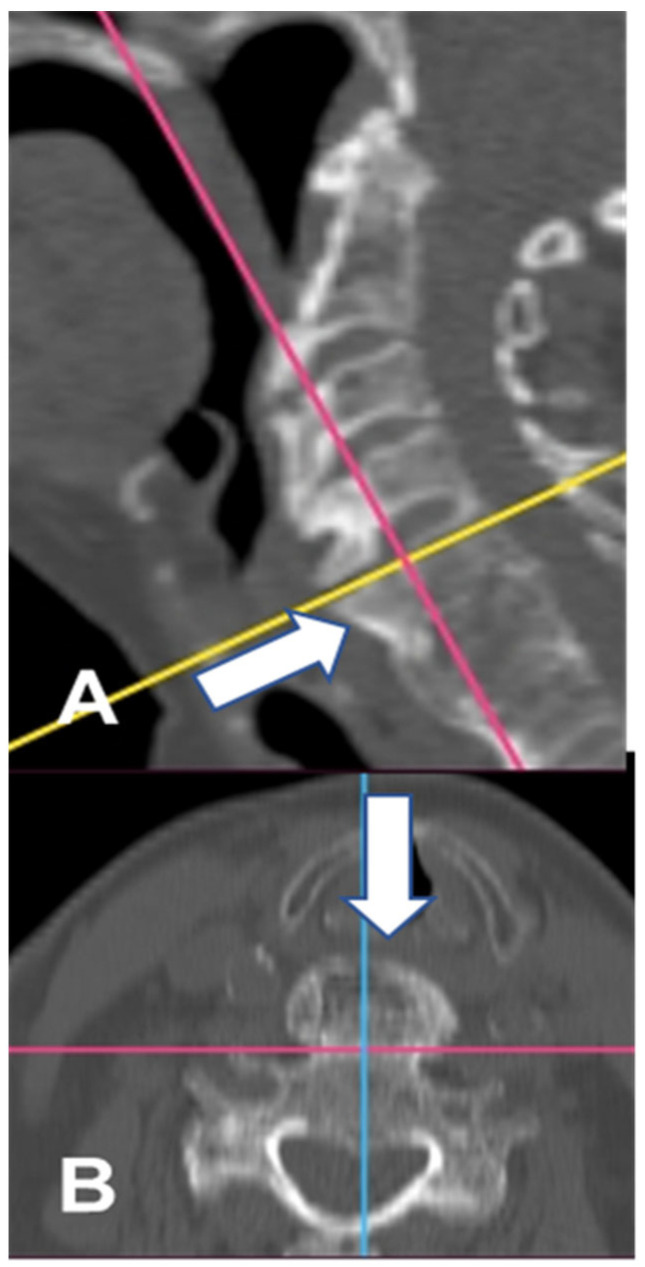

背景/目的:弥漫性特发性骨骼肥厚症(DISH)也被称为foretier - rotes - querol综合征。DISH的病因尚不清楚。DISH的特点是脊柱前纵韧带骨化。该疾病最常累及的区域是脊柱的胸椎区域。DISH在大多数情况下是无症状的。如果颈椎受累,最常见的症状是吞咽困难和呼吸困难。颈椎区的骨化最常发生在脊柱的下节段。病例报告:作者报告了一位92岁的女性病毒症患者(身体质量指数(BMI)为17;在过去的6个月里她的体重减少了13%)。患者行前骨赘C2-T1切除术。结果:在一年的随访中,患者体重增加(BMI-20),并恢复了固体食物的摄入能力。据我们所知,这是接受DISH手术治疗的年龄最大的患者。结论:老年患者如出现吞咽困难或呼吸困难,应进行颈椎检查。如果诊断为DISH是安全的,则应考虑有效的手术治疗。

Background/Objectives: Diffuse idiopathic skeleton hyperostosis (DISH) is also known as Forestier-Rotes-Querol syndrome. The etiology of DISH is unknown. DISH is characterized by ossification of the anterior longitudinal ligaments of the spine. The area most frequently involved in the disease is the thoracic region of the spine. DISH in most cases is asymptomatic. If the cervical spine is involved, the most common symptoms are dysphagia and dyspnea. The ossifications in the cervical region of the spine are localized most frequently in its lower segments. Case presentation: The authors present the case of a 92-year-old cachectic female patient (body mass index (BMI) of 17; lost 13% of her body weight within the last 6 months). The patient underwent resection of the anterior osteophytes C2-T1. Results: At one-year follow up, the patient had gained weight (BMI-20) and regained her ability to consume solid products. To our knowledge, this is the oldest patient treated surgically for DISH. Conclusions: If dysphagia or dyspnea appears among elderly patients, cervical spine inspection should be conducted. If DISH is diagnosed safe, effective surgical treatment should be considered.